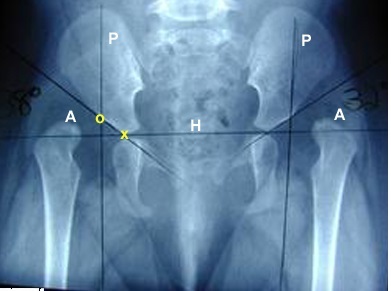

What is H and how does it help evaluate DDH?

Hilgenreiners Line

A normal head should be below it.